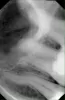

Отпал кусочек зуба (верхняя шестерка), болезненных ощущений не было. После осмотра врач констатировал острый кариес, мне удалили нерв, почистили канал, положили лекарство и поставили временную пломбу на неделю. Через 40 минут после данной процедуры при наклоне из левой ноздри полилась жидкость грязно-розового цвета и резкого неприятного запаха (типа хлорки или какого-либо лекарства). Второй день периодически жидкость выходит из носа.

Сегодня была на приеме, сделали снимок, сказали ничего страшного - просто лекарство попало в гайморовые пазухи. Прописали антибиотики. Зуб не беспокоит, но кусать на него очень больно. У меня маленький ребёнок на ГВ, приём антибиотиков подразумевает прекращение кормления, но это очень серьёзная проблема для меня.

Действительно ничего в этом страшного нет, доктор слишком сильно расширил верхушку корня и тем самым открыл прямой доступ паркана (кислота) в гайморовую пазуху. Антибиотики вам пить нельзя, и дело не только в однократном отказе от вскармливания. Если боли и беспокойств особых нет, то постарайтесь потерпеть.